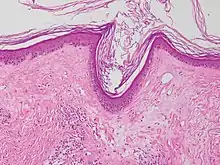

![]() Microfotografía de liquen escleroso que muestra la esclerosis subepitelial característica (derecha/abajo de la imagen). Tinción hematoxilina-eosina. | ||

Se puede hacer una biopsia de la piel afectada para confirmar el diagnóstico. Cuando se hace una biopsia, la hiperqueratosis, la epidermis atrófica, la esclerosis de la dermis y la actividad de los linfocitos en la dermis son hallazgos histológicos asociados con LS.[21] Las biopsias también se revisan para detectar signos de displasia.[22]